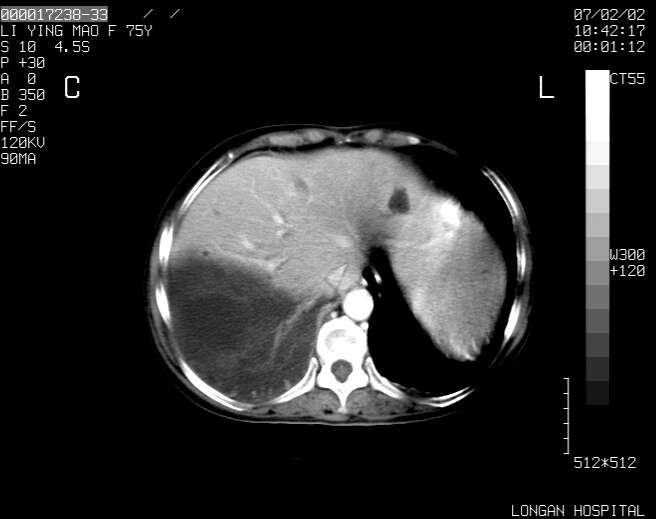

以下是引用dyqct在2007-2-10 8:53:00的发言:[br]考虑:1、肝脏多发囊肿[br] 2、左肾囊肿,右肾多发结石并积水。[br] 3、右胸少量积液。[br] 4、右肾周包裹性积液或淋巴管瘤(有见缝就钻的征象、薄隔、小结节状钙化)?[br] 5、腰椎动脉瘤样骨囊肿?[br] [br] [br]